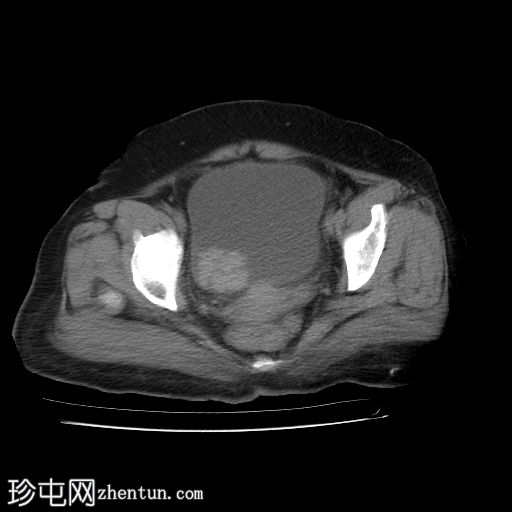

静脉注射造影剂轴位

增强扫描

2.jpg

膀胱内可见一边界清晰、不规则、可移动的软组织病变(CT值65 HU),直径约40 mm。病变无钙化,增强扫描后无强化。首要鉴别诊断为血肿。